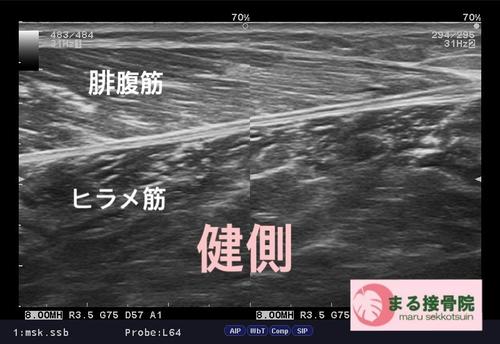

治療は、しっかり問診、触診、視診を行い、超音波画像診断装置で患部状態、深さ、広さをしっかり確認し、早期復帰、回復に向けて対処していきます。

まずは患部の出血、腫れを最小限に抑え、周囲の筋肉も硬くならないようにし、タイミングを診てストレッチ、リハビリを行って参ります。